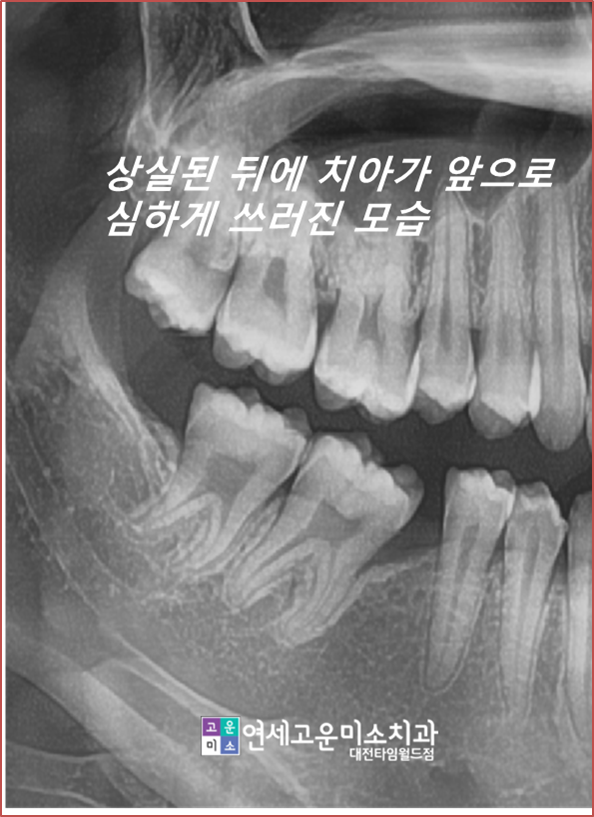

case2) 임플란트를 심어야 되는데 공간이 없어요

치아가 상실되고 나고 시간이 오래 지나면

위에 엑스레이처럼 옆에 치아가 그 공간으로 쓰러지게 됩니다.

저 상태에서는 임플란트를 할 수 없기 때문에

교정을 하지 않는다면

쓰러진 치아를 신경치료를 하고 씌운 뒤

임플란트를 하게 됩니다.

-->하지만 이렇게 치료를 하면

건전한 치아를 삭제해야 하는 단점이 생기고

쓰러진 채로 임플란트를 하기 때문에

음식물도 잘 낍니다.